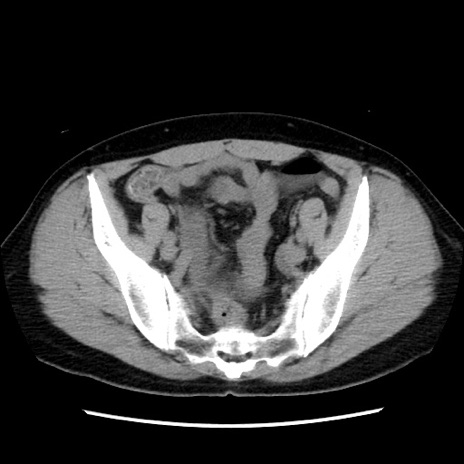

症例10(横断像)

【症例】 50歳代女性

【主訴】 腹痛

【現病歴】前日生レバーを食べた。今朝に排便あり。 昼前に突然発症の腹痛を生じ、当院救急外来を受診した。

【既往歴】 子宮筋腫にてで子宮全摘後

【身体所見】 意識清明、腹部:平坦、軟、下腹部やや左を中心に圧痛・反跳痛あり、筋性防御あり

【データ】WBC 7800、CRP 0.07